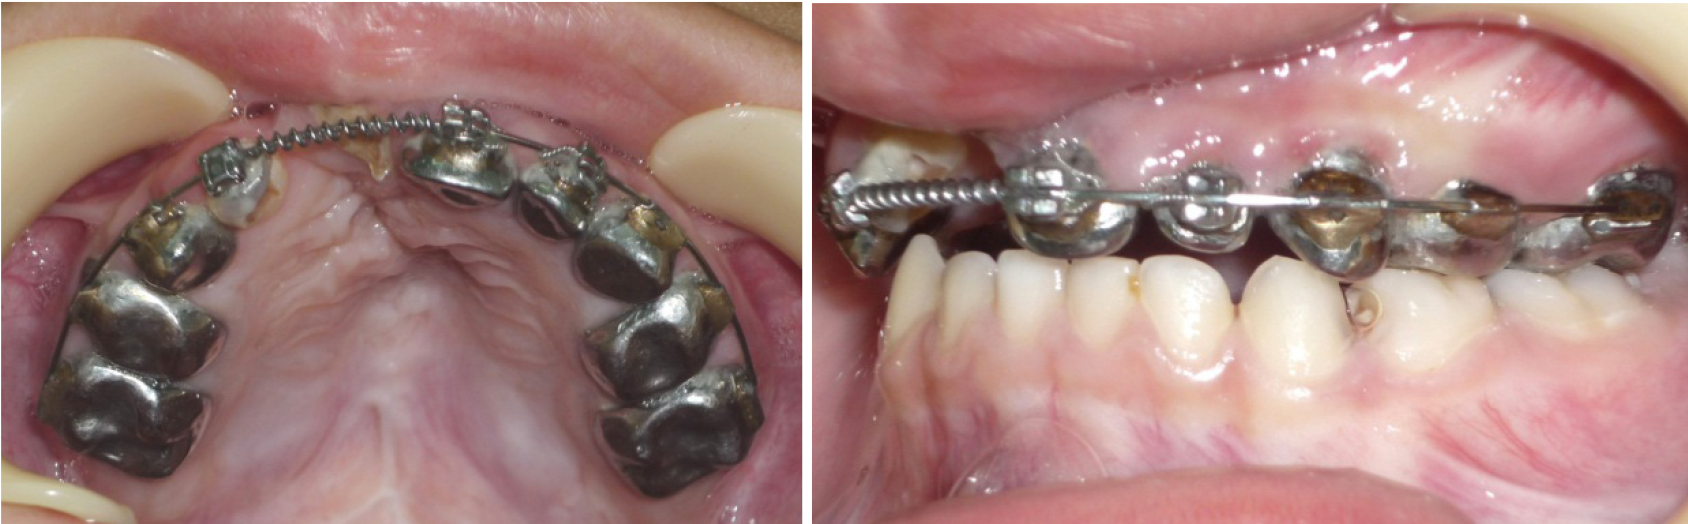

Лечение проводилось с применением несъемной дуговой аппаратуры. Фиксирующими элементами служили тонкостенные коронки (кольца) с припаянными вестибулярными брекетами. Размер металлической дуги определяли с помощью предложенных методов графического анализа (рис. 3). Металлические дуги меняли с учетом протокола лечения эджуайс-техникой до нормализации формы арки, соответствующей прогнозируемым размерам. После нормализации окклюзионных взаимоотношений аппарат использовался в качестве ретенционного до смены молочных зубов постоянными (рис. 4).

Рис. 3. Построение формы верхней зубной арки при врожденной аномалии для определения размеров металлических дуг